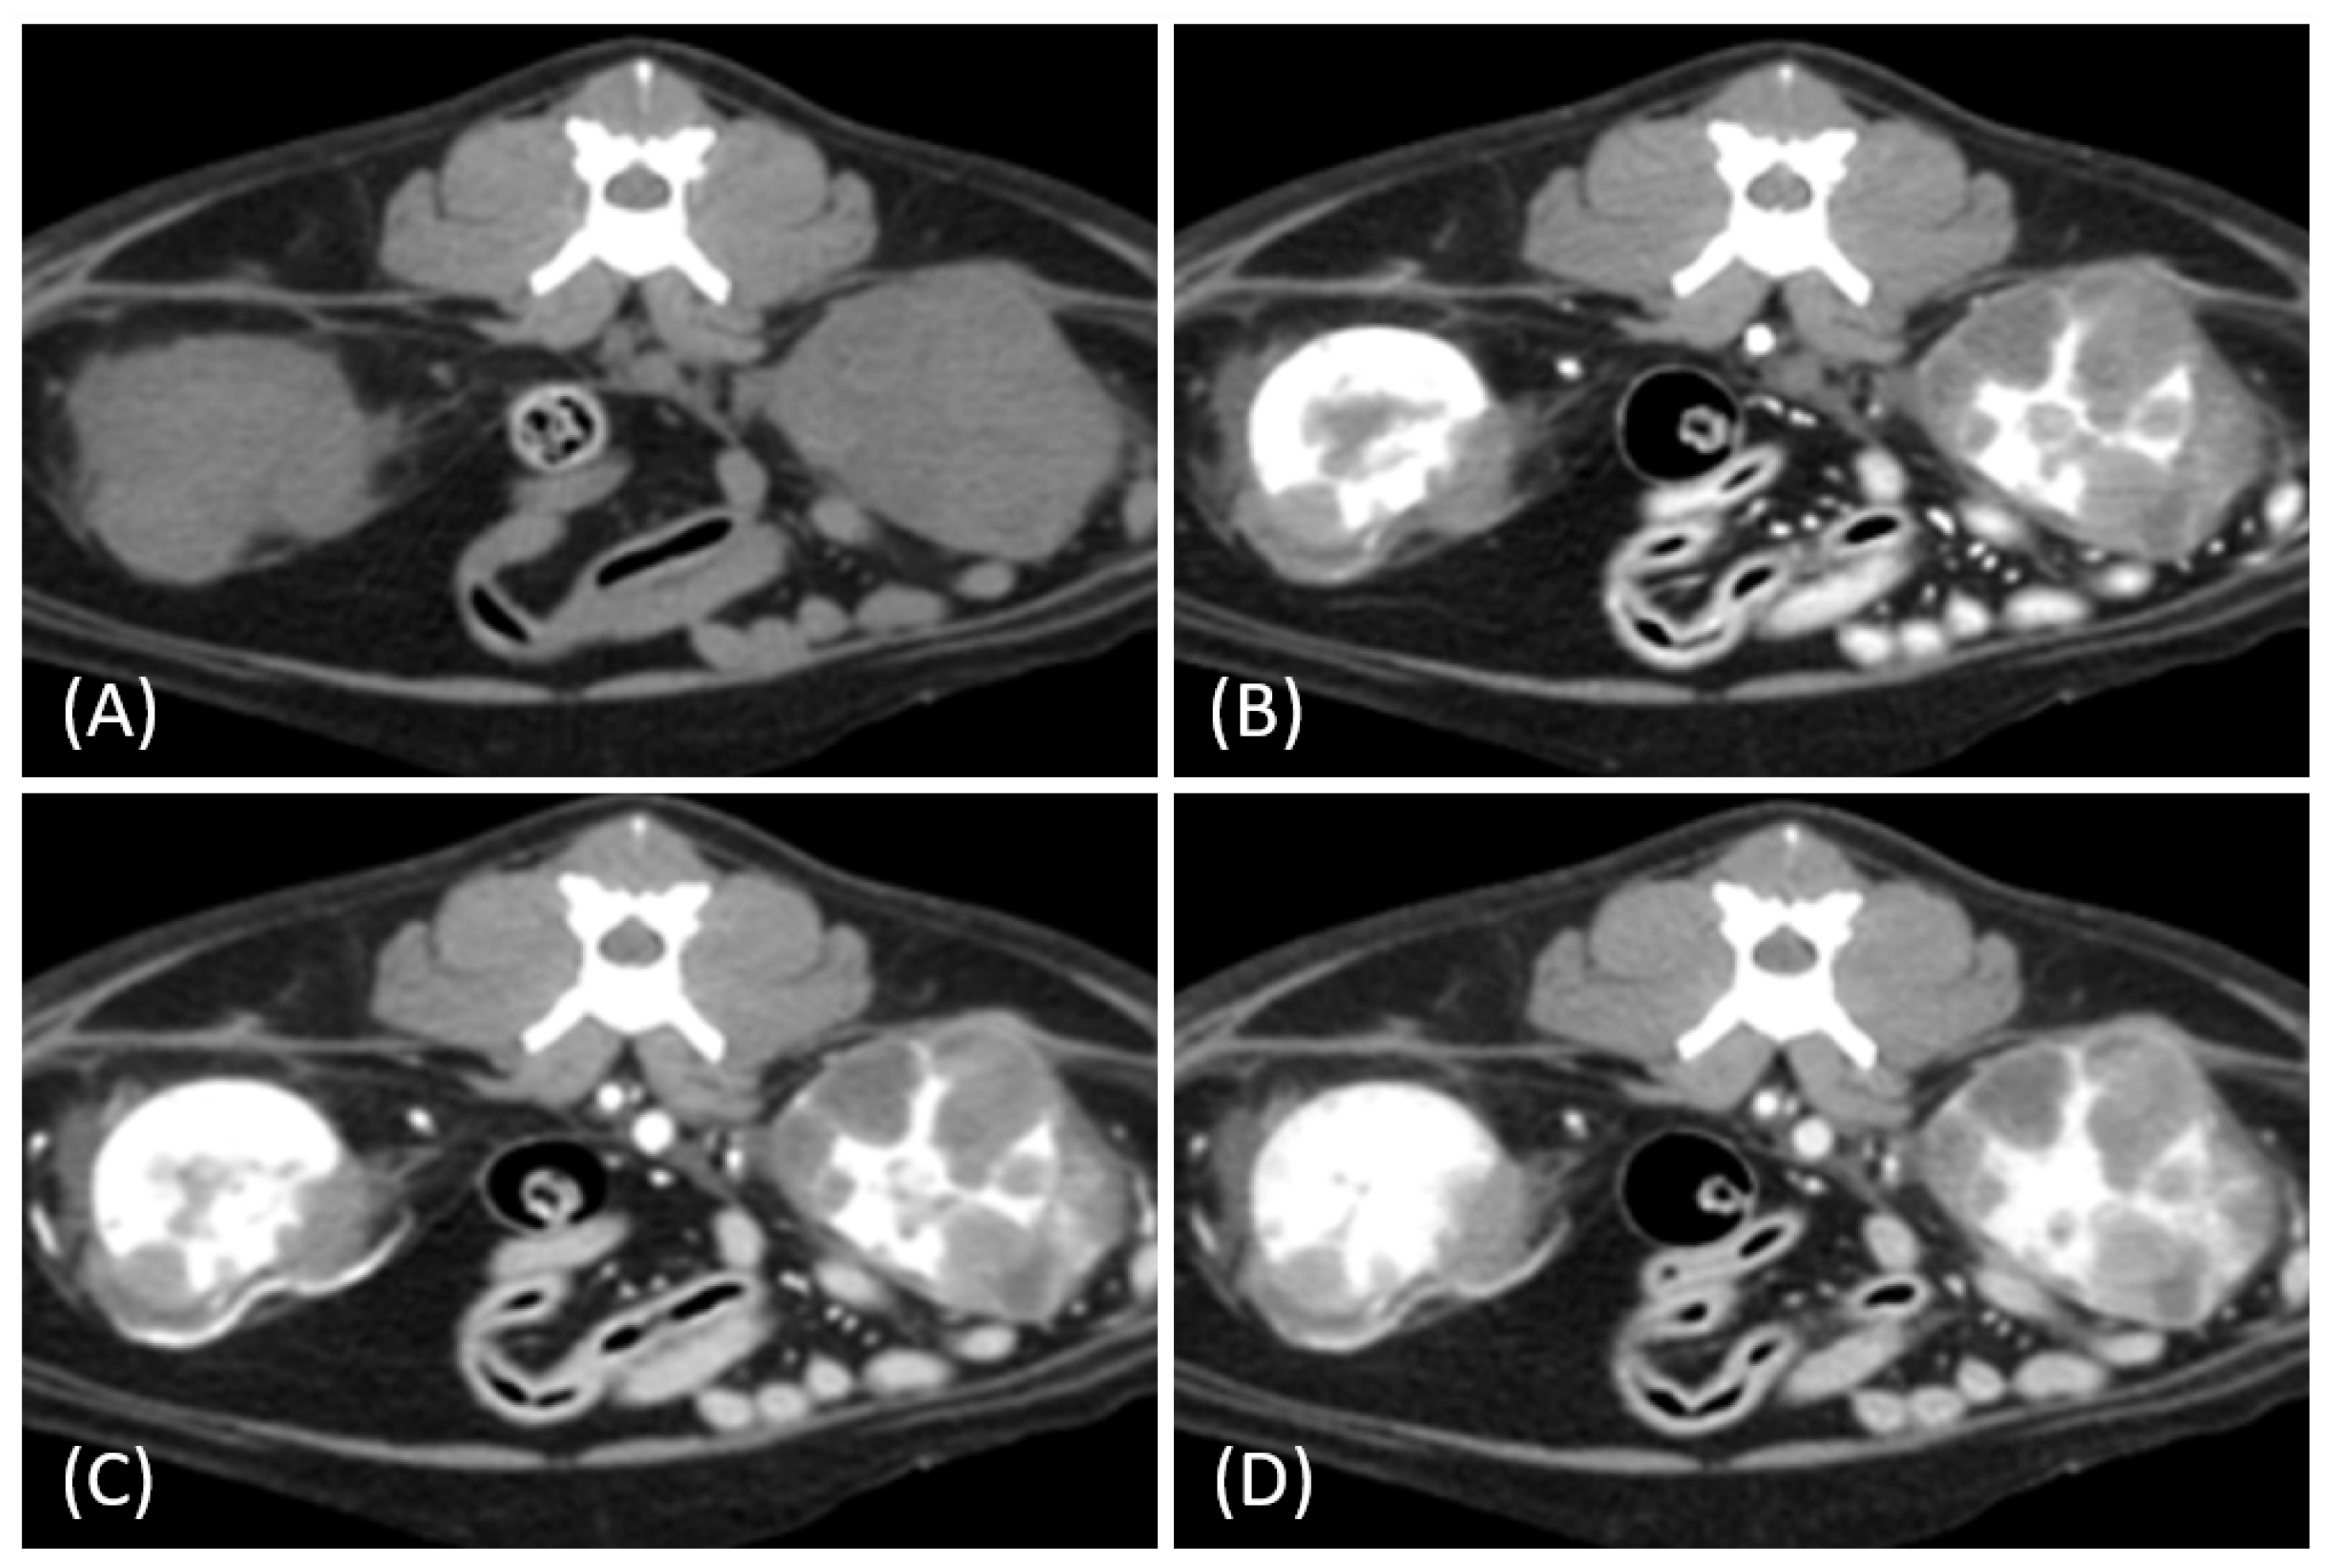

Figure 6.

Contrast-enhanced computed tomography (CT) images of renal tumors in different cats. (A) Lymphoma with a heterogeneous and irregular appearance. (B) Papillary renal cell carcinoma (RCC) presents as a relatively hypoenhancing mass, mimicking the solitary hypoenhancing mass observed in the lymphoma. Partially nonenhancing hypoattenuating regions corresponded to extensive internal necrosis observed in the histopathological analysis. (C,D) Incidental findings of small RCCs in two different cats demonstrating increased vascularity and heterogeneity without significant alteration of kidney shape.

In the two cats that were excluded, the RCC tumors showed a distinct imaging pattern with rim enhancement but no internal enhancement on contrast-enhanced CT (Figure 7). The attenuation values of the tumors were approximately 23 HU and 33 HU across both the pre- and post-contrast phases.

Figure 7.

(A) Pre-contrast and (B) late nephrographic/early excretory phase contrast-enhanced computed tomography (CT) images of a renal cell carcinoma (RCC). The image shows a large renal mass with rim enhancement and no internal enhancement. Vascular structures such as the aorta (white arrow) and CVC (black arrow) are visible; however, the renal artery and vein are not clearly identifiable. Tumor invasion into adjacent musculature is observed (arrowhead).